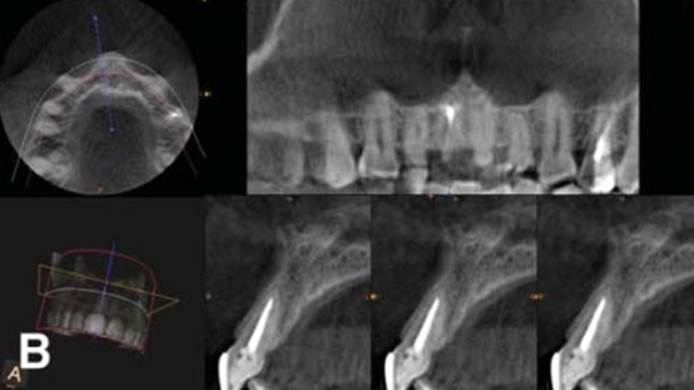

Clinical case: Single molar implant with bone augmentation

- Courtesy of Dr. Jung Sam Lee, Korea -

Keywords

AnyOne, bone augmentation, osteotomy socket, peri-implant tissue, autogenous bone, GBR, single replacement, Auto-Max, Dr. Jung Sam Lee

Products:

AnyOne implant system, Auto-Max